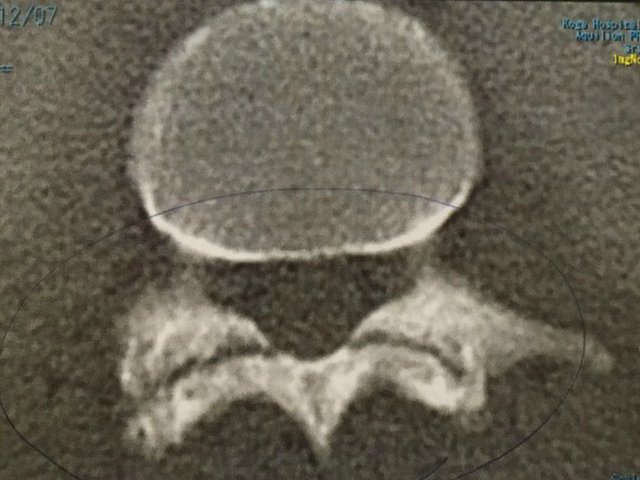

この3D CT画像は、下記の圡居ノ内君のものです。

左側が2017年12月7日撮影。黒い横線が入っていて、骨が分離していることが分かります。この時点ではまだ少し痛みが残っていました。

その後同年12月下旬には痛みがない状態になり、2018年1月に2回施術して終了しました。

2018年3月1日再検査したのが右側の画像です。分離しているところが分からないくらい綺麗にくっついています。検査結果を聞いたお父様から喜びの電話を頂きました。